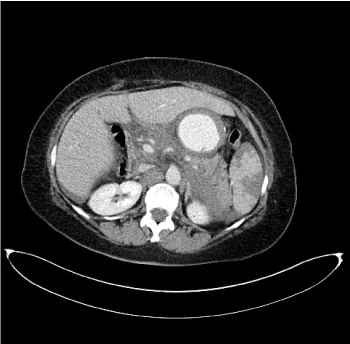

CT Imaging findings suggested the presence of splenic artery aneurysmatic dilatation, which can’t be separeted from the gastric wall, close to surgical clips of the previous Sleeve gastrectomy (Figure 1). A mediastinal hematoma constricted the esophagus (Figure 2). Fat stranding of the retroperitoneal space, hemoperitoneum (Figure 3) and ischemic injuries of the spleen were present (Figure 4).

Figure 3. CT axial image after intravenous injection of iodinated contrast agent at the pelvis shows the presence of fluid collection due to hemoperitoneum

Figure 4. CT axial image after intravenous injection of iodinated contrast medium: evidence of hypodense triangular areas from the splenic hilum to the periphery, of the spleen due to ischemic injury